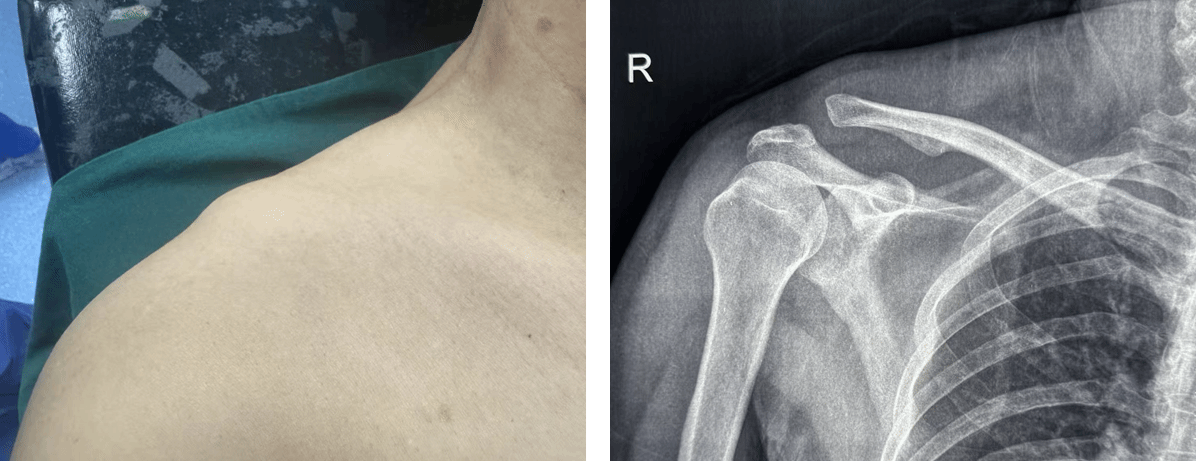

术前:被锁住的肩膀

三个月前,王先生不幸发生车祸,车祸后导致其锁骨高高翘起,现今肩膀疼得无法动弹,已经影响正常生活。王某经多方打听后,就诊于西安交通大学第二附属医院骨科中心运动医学门诊,接诊医生倪建龙诊断王某属于“肩锁关节Rockwood V型脱位”的重度陈旧性损伤,X光片检查显示:右侧锁骨远端像翘起的屋檐般高高耸起,与肩胛骨分离,这是典型的高能量肩锁关节脱位。“好比连接锁骨和肩胛骨的‘天然铆钉’(喙锁韧带)完全断裂。”倪建龙副主任医师解释:“传统钩钢板好比用铁片强行压住锁骨,不仅创伤大,术后常伴随肩关节疼痛和僵硬。”